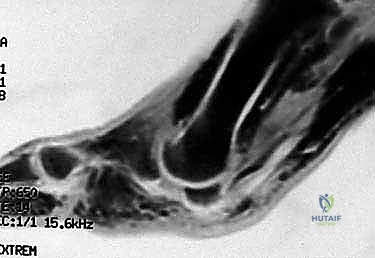

* MRI: While more expensive, MRI provides excellent soft tissue detail, allowing us to identify most causes of hallux MTP pathology, including osteonecrosis, stress fractures, tendinosis, bursitis, and articular cartilage damage, in addition to sesamoiditis.

Figure 2: A sagittal MRI view of the sesamoid-metatarsophalangeal complex, illustrating the increased stress across the tibial sesamoid during MTP dorsiflexion.